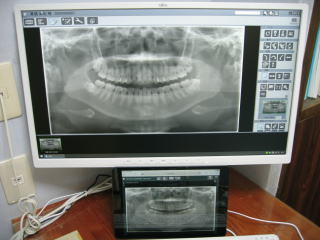

令和3年8月、平成元年の開業以来、約33年間お世話になったアナログレントゲン2台に別れを告げ、

最新式のデジタルレントゲン2台(全体のパノラマ、一部分のデンタル)を導入しました。

患者さんの被ばく量は従来の1/5〜1/10以下となり、より安全性が増しました。

なおかつ、短時間で鮮明な画像が得られ、診断や治療に大いに役立ち、患者さんにも好評です。

700万円を超える高額なレントゲン装置で支払は大変ですが、とても重宝しています。